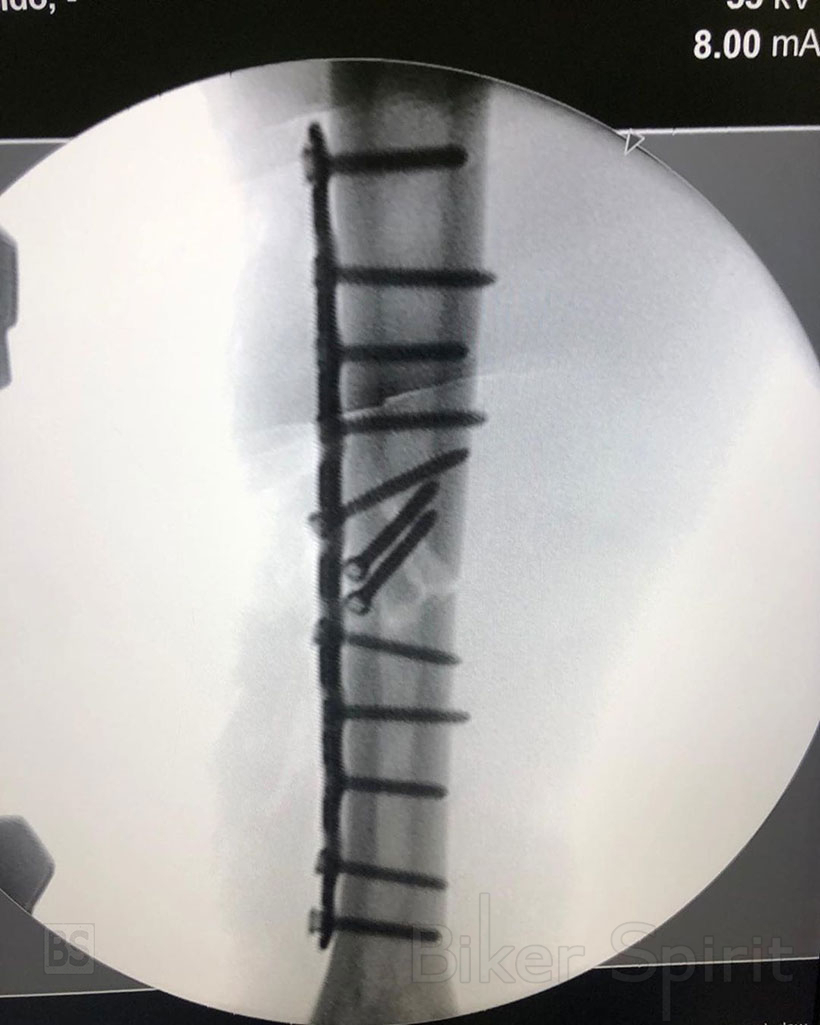

Σήμερα το πρωί ο Ισπανός οδηγός δημοσίευσε κάποιες εικόνες στα κοινωνικά του κανάλια που συνοψίζουν την εβδομάδα που μόλις πέρασε. Ο Marquez εμφανίστηκε χαμογελαστός μαζί με τον γιατρό που τον χειρούργησε και έδειξε επίσης μια ακτινογραφία με το χέρι του μετα την εγχείρηση και γεμάτο βίδες και το σπασμένο κόκαλο του σε μια τρισδιάστατη απεικόνιση σε ένα βίντεο.

Η συλλογή των εικόνων συνοδεύτηκε από το ακόλουθο σχόλιο: «Καλημέρα σε όλους! Ξεκινήσαμε μια νέα εβδομάδα με μεγάλη δύναμη, αλλά πρώτα θέλω να σας αφήσω μια φωτογραφική περίληψη της προηγούμενης.»